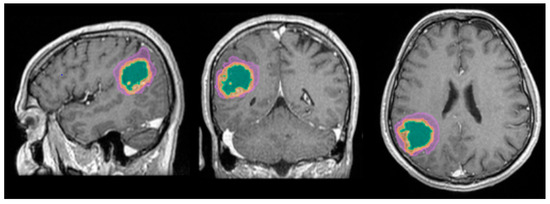

A better identification of cystic components and necrotic central tissue could be obtained by analyzing the contour defined by the lesion border, as necrotic borders are irregular and anfractuous, differing in thickness. In contrast, cystic walls are well delineated and smooth, having a more rounded shape (see Figure 10) [20].

Figure 10.

Mdbrain processing of MRI brain acquisition (DICOM). (a) T1W CE +FLAIR (Scale 1:24), axial plane, green area corresponding to the cystic portion of the lesion; (b) T1W CE + FLAIR (Scale 1:20), axial plane, green area corresponding to the necrotic center (approval was obtained from the Ethics Committee of the University of Medicine and Pharmacy “Grigore T. Popa” Iasi).